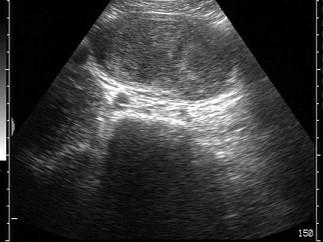

问题 男性,右侧阴囊空虚,左侧可触及,于腹腔见一个椭圆形低回声光团,边界清晰,回声尚均匀,CDFI:血流信号丰富。如图所示,考虑为 ?(?)

选项 A.隐睾并精原细胞瘤 B.腹腔囊肿 C.腹腔淋巴结 D.畸胎瘤 E.腹腔淋巴瘤

答案 A